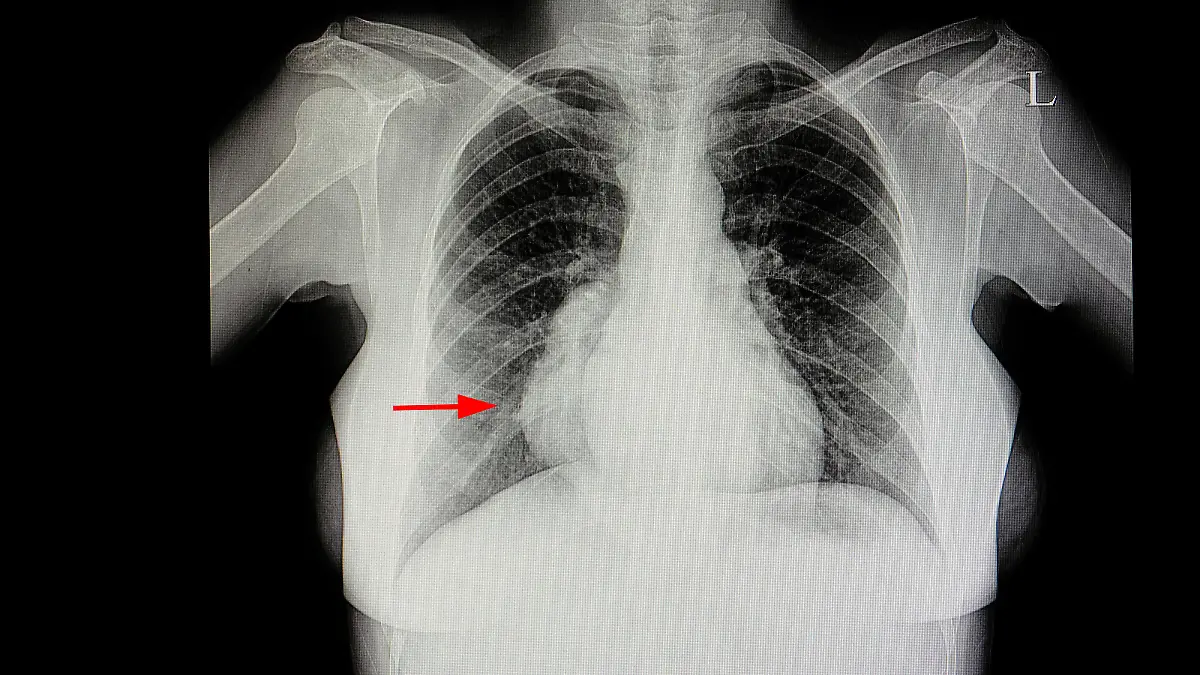

Da das Mediastinum wichtige Organe und Strukturen enthält, können sich dort unterschiedliche Erkrankungen ergeben. Allgemeine Bedeutung haben die Mediastinaltumoren sowie die Mediastinalverschiebung. Bekannte Mediastinaltumoren sind unter anderem Lymphome oder Thymome. Bei beiden Tumorarten gibt es benigne (gutartige) oder maligne (bösartige) Formen. Alle Mediastinaltumoren zeigen typische Symptome, die aus der Verdrängung von benachbarten Organen und Strukturen resultieren. So treten zunehmende Heiserkeit, Zwerchfellhochstand, Husten, Atemnot, Atemnebengeräusche und das sogenannte Horner-Syndrom mit Verengung der Pupillen, hängenden Augenlidern und Augapfelschwund auf. Bei der Mediastinalverschiebung wird der Mittelfellraum durch Raumforderung, etwa durch einen Pneumothorax, in eine Thoraxhälfte verschoben. Bei massiven Verschiebungen sind chronische Atemwegsprobleme möglich.